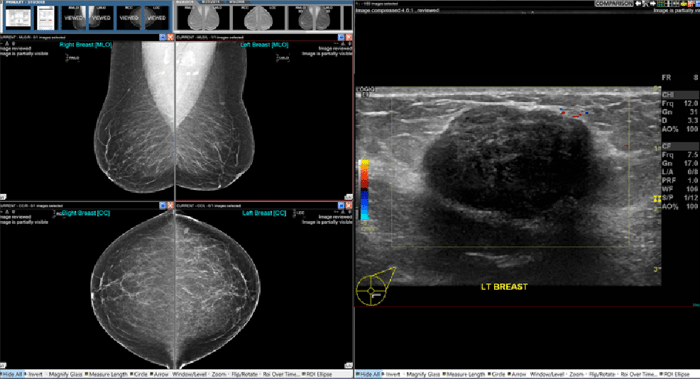

Integrated mammography viewer that enables you to ergonomically read a wide variety of breast imaging studies as well as studies from all other specialties all in one place. NovaMG Pro can be a stand alone solution that works with any PACS or be added to Novarad's enterprise imaging software.

2D and 3D breast Imaging

Essential for providing detailed, multi-dimensional views that are crucial for the early detection and accurate diagnosis of breast conditions.